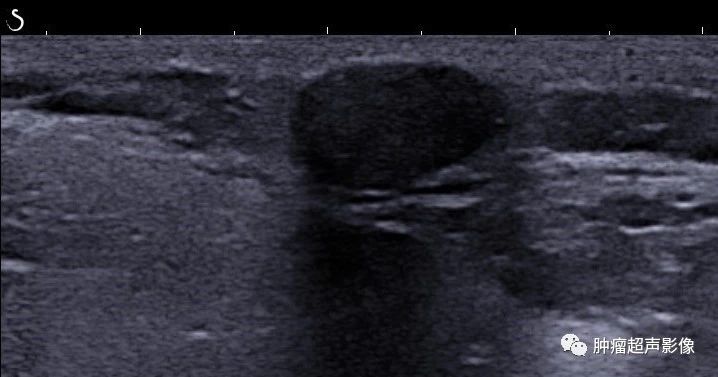

小孩耳后可移动无痛性肿块,皮肤真皮与皮下脂肪层交界处见强回声,边界清,后伴宽大声影,符合典型毛母质瘤的特点(图片来自会诊病例)。